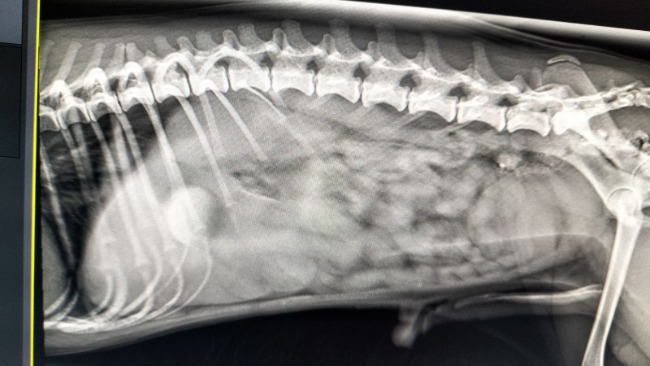

Niestety parę dni temu wydarzył się wypadek. Junior podczas zabawy połknął piłeczkę kałczukową... Ugrzęzła mu i jest z nim coraz gorzej... Wymiotuje, nie ma na nic siły. Co gorsza jak najszybszą operacja kosztuje od 2500 w górę.